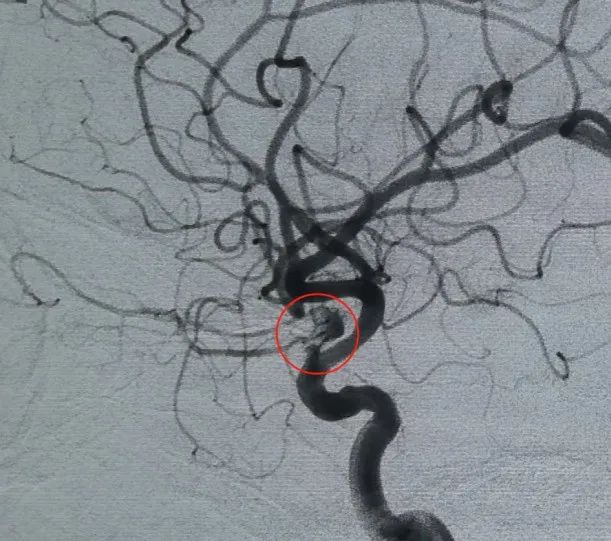

Diagnosis: Left internal carotid artery C6 segment ophthalmic artery aneurysm

Vascular access was established via femoral artery puncture, and a Perdenser® 6 mm × 20 cm 3D coil was first deployed to form a basket, achieving stable wall apposition and providing secure intrasaccular support. This was followed by the insertion of a Perdenser® 6 mm × 15 cm 3D coil to disrupt blood flow within the lobulated daughter sac.